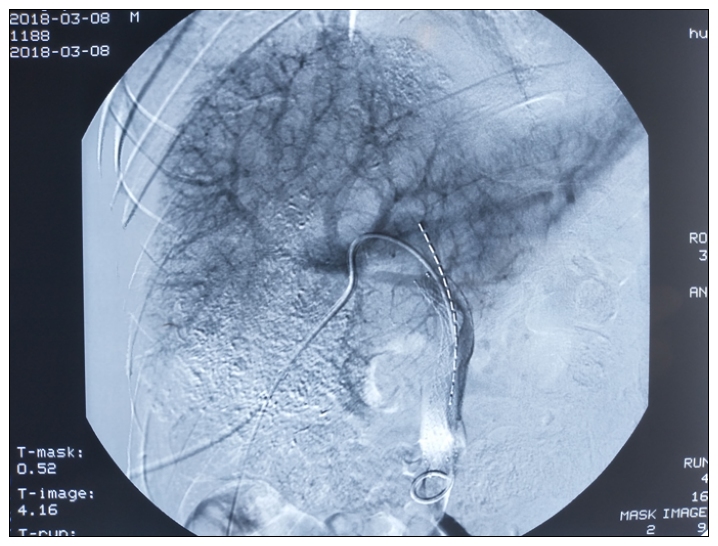

具体方法是:肝脏内的肝癌主要通过肝动脉供血,故通过肝动脉途径向肿瘤供血动脉注射化疗药物和栓塞剂对肿瘤进行化疗栓塞(传统的TACE术),能够得到控制;肝动脉栓塞对门静脉癌栓疗效不佳,且门静脉癌栓阻塞门静脉可致正常肝脏缺血导致肝功能不全或衰竭,故穿刺门静脉放置支架立即开通闭塞或者狭窄的门静脉,保证正常肝脏的门静脉血流,并在有癌栓的那一段门脉壁和支架之间放置放射性粒子。利用粒子持续释放的短程射线对癌栓进行近程放疗,这一方法能同时控制肝内肿瘤和门脉癌栓,该治疗方法已经被写入“肝细胞癌合并门静脉癌栓多学科诊治中国专家共识(2016版)”。